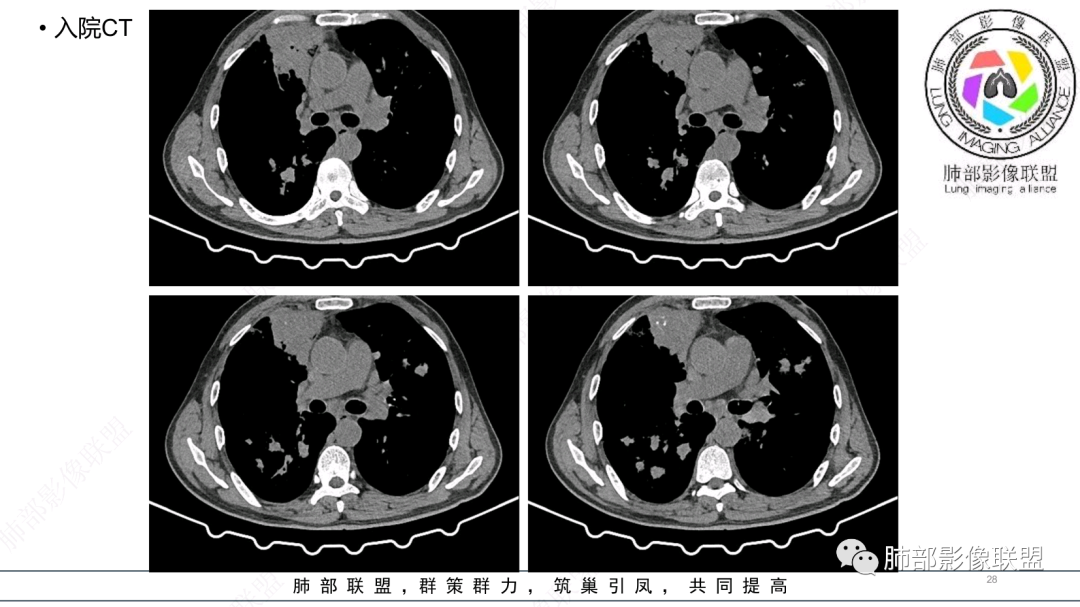

中老年男性,发病一周,发热,炎症指标明显增高,双肺支气管扩张基础,双肺可见多发结节、斑片状、团块状密度增高,边缘尚清。病灶分布与支气管关系密切,考虑支扩合并感染,铜绿,NTM、奴卡、曲霉等,环卫工人,可能接触腐败物较多,考虑曲霉可能大,鉴别奴卡。

男性,56岁,清洁工,临床表现咳嗽咳痰发热。胸部影像:两肺散在斑片、结节及实变影,大部分沿气道分布,以下肺为著并伴发多发支气管扩张及囊腔影,实验室检查白细胞增高,考虑感染性病变,曲霉、铜绿及NTM。

56岁,工作性质:环卫工人。主诉:咳、痰、喘、发病一周。急性起病(或者慢病+AE),呼吸道感染症状。化验指标白细胞、中性、CRP明显升高。影像学显示多灶性,有柱状支扩,囊状支扩等结构肺病,责任细菌主要考虑铜绿假单胞菌,不排除合并其他细菌以阴杆为主;存在树芽影,发热,炎症沿支气管束分布,是否合并TB?真菌?;树芽伴发热支原体感染也要需要考虑进去;全肺多灶性炎症,部分病灶周围有晕,右上叶疑似反晕,内部疑似有丝,右下肺考虑存在粘液栓,加之环卫工工作性质,考虑霉菌,主要考虑曲霉。

两肺支扩,两肺沿支气管分布多发结节、树芽及团块,边缘模糊,部分支气管管壁增厚,考虑气道侵袭性曲霉菌,鉴别铜绿、奴卡、结核。

支气管壁增厚,晕征明显,病灶沿着支气管纵向分布,结合患者职业,考虑气道侵袭性曲霉。

多发结节,部分结节边缘清楚,部分边缘模糊,支扩合并肉芽肿性炎,奴卡菌与曲霉之间选择。

影像改变为支扩伴气道来源感染,部分实变性伴有小脓肿及钙化,结合PCT及白细胞、中性粒明显增高,符合细菌感染,首先考虑奴卡,绿脓次之,因为临床有喘息、影像实变性有钙化,加上环卫工这一职业史,需要鉴别曲霉或奴卡合并曲霉。